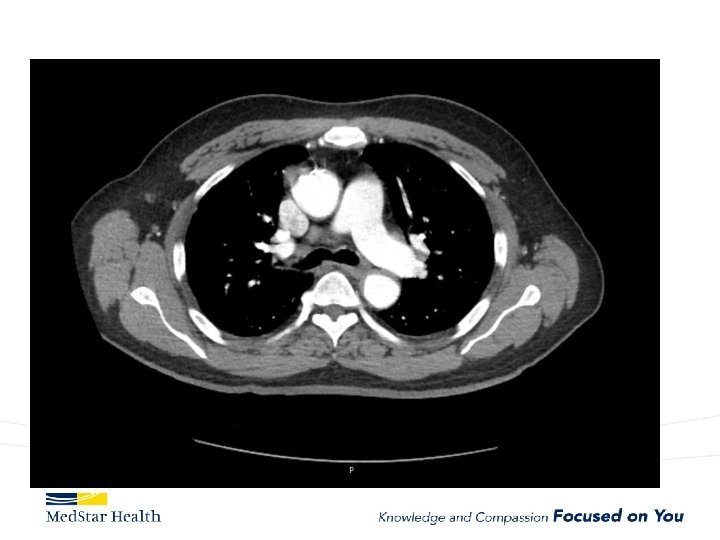

Acute Type B Aortic Dissection • Incidence: 2. 6 -3. 5 per 100, 000 patient-year • Uncomplicated • Complicated – – Malperfusion Rupture Unremitting Pain Uncontrolled HTN

How Do We Treat • Open repair-unacceptable morbidity and mortality • TEVAR – Improved morbidity and mortality – Coverage of primary entry tear – Additional coverage?

Type B Dissection Complicated Uncomplicated Risk TEVAR age, comorbidities Extreme Low Medical Management False Lumen Small, Thrombosed Medical Management Patent/Large(>22 mm), Total Aorta >40 mm TEVAR/adjuncts